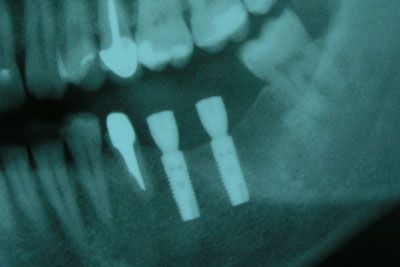

От протезирования с помощью мостовидной конструкции (в этом случае обтачиваются соседние здоровые зубы и на них ставятся опорные коронки) он отказался. Для выполнения надежной мостовидной конструкции нам пришлось бы обточить три зуба 34, 35 и 38, два из которых еще и депульпировать. С предложением установить два винтовых имплантата и последующем изготовлением металлокерамических коронок пациент согласился. Под местной анестезией была произведена установка двух винтовых имплантатов Astra Tech с одномоментной постановкой формирователей десны.

Через четыре месяца было выполнено протезирование, изготовлено две коронки на имплантаты и одиночная коронка на 35 зуб. Функция жевания восстановлена полностью.